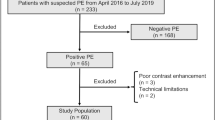

A total of 116 patients with suspected acute PE and 55 patients with CTEPH were included. Of these 171 patients, 32 were excluded: 11 patients due to too low intraarterial contrast (mean attenuation in the MPA: 261.1 ± 4.9 HU in included scans vs. 217.3 ± 19.5 HU in excluded scans, p < 0.001), 20 patients from the acute PE arm with subacute PE based on patient´s medical history or imaging features, and one patient with a tumorous vascular occlusion (Fig. 1). There were no differences between the groups regarding age (mean ± SD: acute PE, 61 ± 16 years; CTEPH, 62 ± 16 years; controls, 63 ± 18 years; p = 0.76). While gender distribution between the acute PE (m/f, 32/25) and the CTEPH group (m/f, 24/28) was comparable (p = 0.30), controls were more often female (m/f, 5/17) as compared to PE patients (p = 0.008). Percentages of normal perfused and malperfused areas in the lung were 68.6 ± 17.9% and 28.3 ± 18.4%, respectively, for patients with acute PE, 53.6 ± 20.0% and 44.1 ± 20.2%, respectively, for patients with CTEPH, and 73.1 ± 18.2% and 23.9 ± 18.5%, respectively, for controls. There was no difference between groups regarding the number of beam hardening artifacts due to contrast in the subclavian vein and/or extracorporeal foreign material (acute PE, 30/57; CTEPH, 32/52; controls, 14/22; p = 0.54). Manual editing of the generated lung volumes was required in 54 of 131 cases (41.2%) and more frequently necessary in acute PE compared to both other groups (acute PE, 37/57; CTEPH, 15/52; controls, 2/22; p < 0.001).